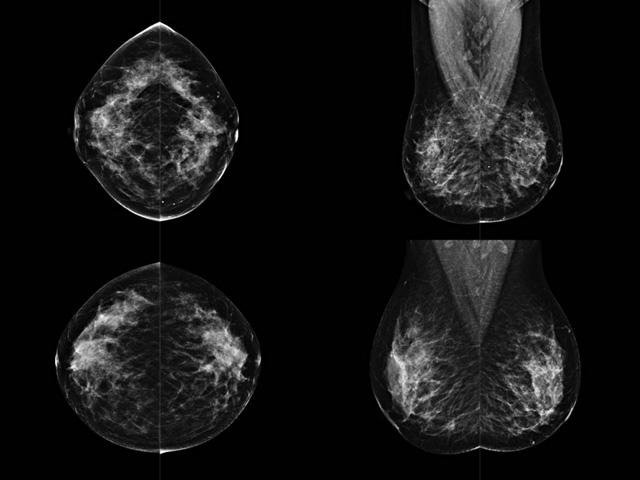

乳腺DR成像設(shè)備中非晶硅跟非晶硒兩種平板探測(cè)器

乳腺DR成像設(shè)備中非晶硅跟非晶硒兩種平板探測(cè)器。更要提供優(yōu)質(zhì)的圖像質(zhì)量乳腺的組織結(jié)構(gòu)與厚度各不相同,減少重拍率輻射劑量,,乳腺的主要構(gòu)成組織均為軟組織結(jié)構(gòu),組織之間密度十分相似,缺乏天然對(duì)比度。選擇軟X線攝影技術(shù)獲得良好對(duì)比度的乳腺結(jié)構(gòu)影像。增加各組織對(duì)X線的吸收差異。乳腺攝影測(cè)和分類,平板探測(cè)器的像素尺寸范圍應(yīng)在50到100μm之間。特別是微鈣化灶可以小到100到200μm,平板探測(cè)器都必極小微鈣化灶進(jìn)行成像。

乳腺DR是利用X光來(lái)做檢查,在一瞬間將被檢測(cè)到的位置投影出來(lái),因?yàn)槭撬查g的輻射,所以只需要0.5秒的時(shí)間。因此對(duì)病人的輻射很低,大約是0.023mSv,比國(guó)家的標(biāo)準(zhǔn)要低得多。DR系統(tǒng)由 X線、發(fā)生裝置、直接轉(zhuǎn)換平板探測(cè)器、系統(tǒng)控制器、影像監(jiān)視器、影像處理工作站等組成。能檢查胸腔積液、肺結(jié)核、大葉性肺炎、肋骨骨折等。心室增大、主動(dòng)脈擴(kuò)張、主動(dòng)脈瘤等心臟病。腹部病變,如腸梗阻、腸穿孔等,DR上可見(jiàn)液氣平面、膈下游離氣腫。DR表現(xiàn)不正常,要結(jié)合臨床表現(xiàn)、體征、癥狀等綜合分析,結(jié)合CT、彩超、血液分析等,才能作出正確的判斷。